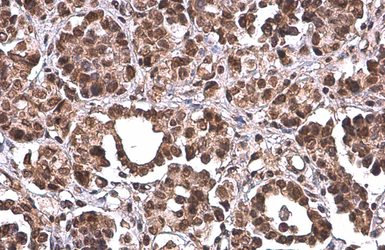

PRMT1 antibody [GT10111] detects PRMT1 protein at cytoplasm and nucleus by immunohistochemical analysis.

Sample: Paraffin-embedded human ovarian cancer.

PRMT1 stained by PRMT1 antibody [GT10111] (GTX630187) diluted at 1:200.

Antigen Retrieval: Citrate buffer, pH 6.0, 15 min